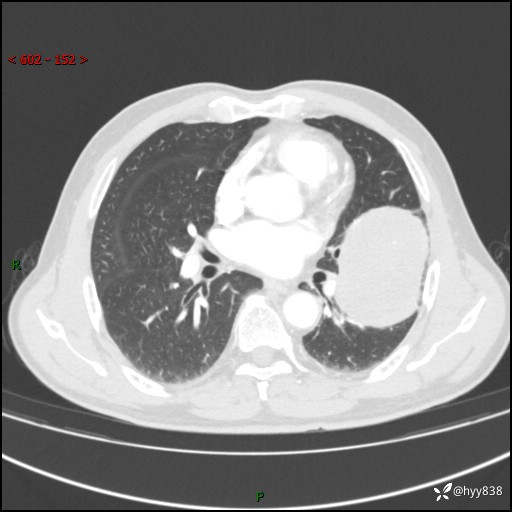

68岁/男,发现左下肺占位5天。如此大的肿块,患者竟然没有症状---结果公布~

【患者信息】:68岁/男

【主诉】:检查发现左下肺占位5天。

【现病史及既往史】:患者于4天前外院行“经尿道钬激光碎石术”,住院期间胸部CT检查发现左下肺肿块,患者平素无明显咳嗽咳痰,无心慌、胸闷、胸痛、呼吸困难、低热、盗汗,无头痛、头晕,无腹痛、腹胀等不适,现患者为求进一步治疗,遂来我院就诊,以“左下肺肿块”收入我科。 患者自起病以来,精神可,睡眠可,饮食可,大小便正常,体重无明显改变。

【检查】:胸部CT增强扫描